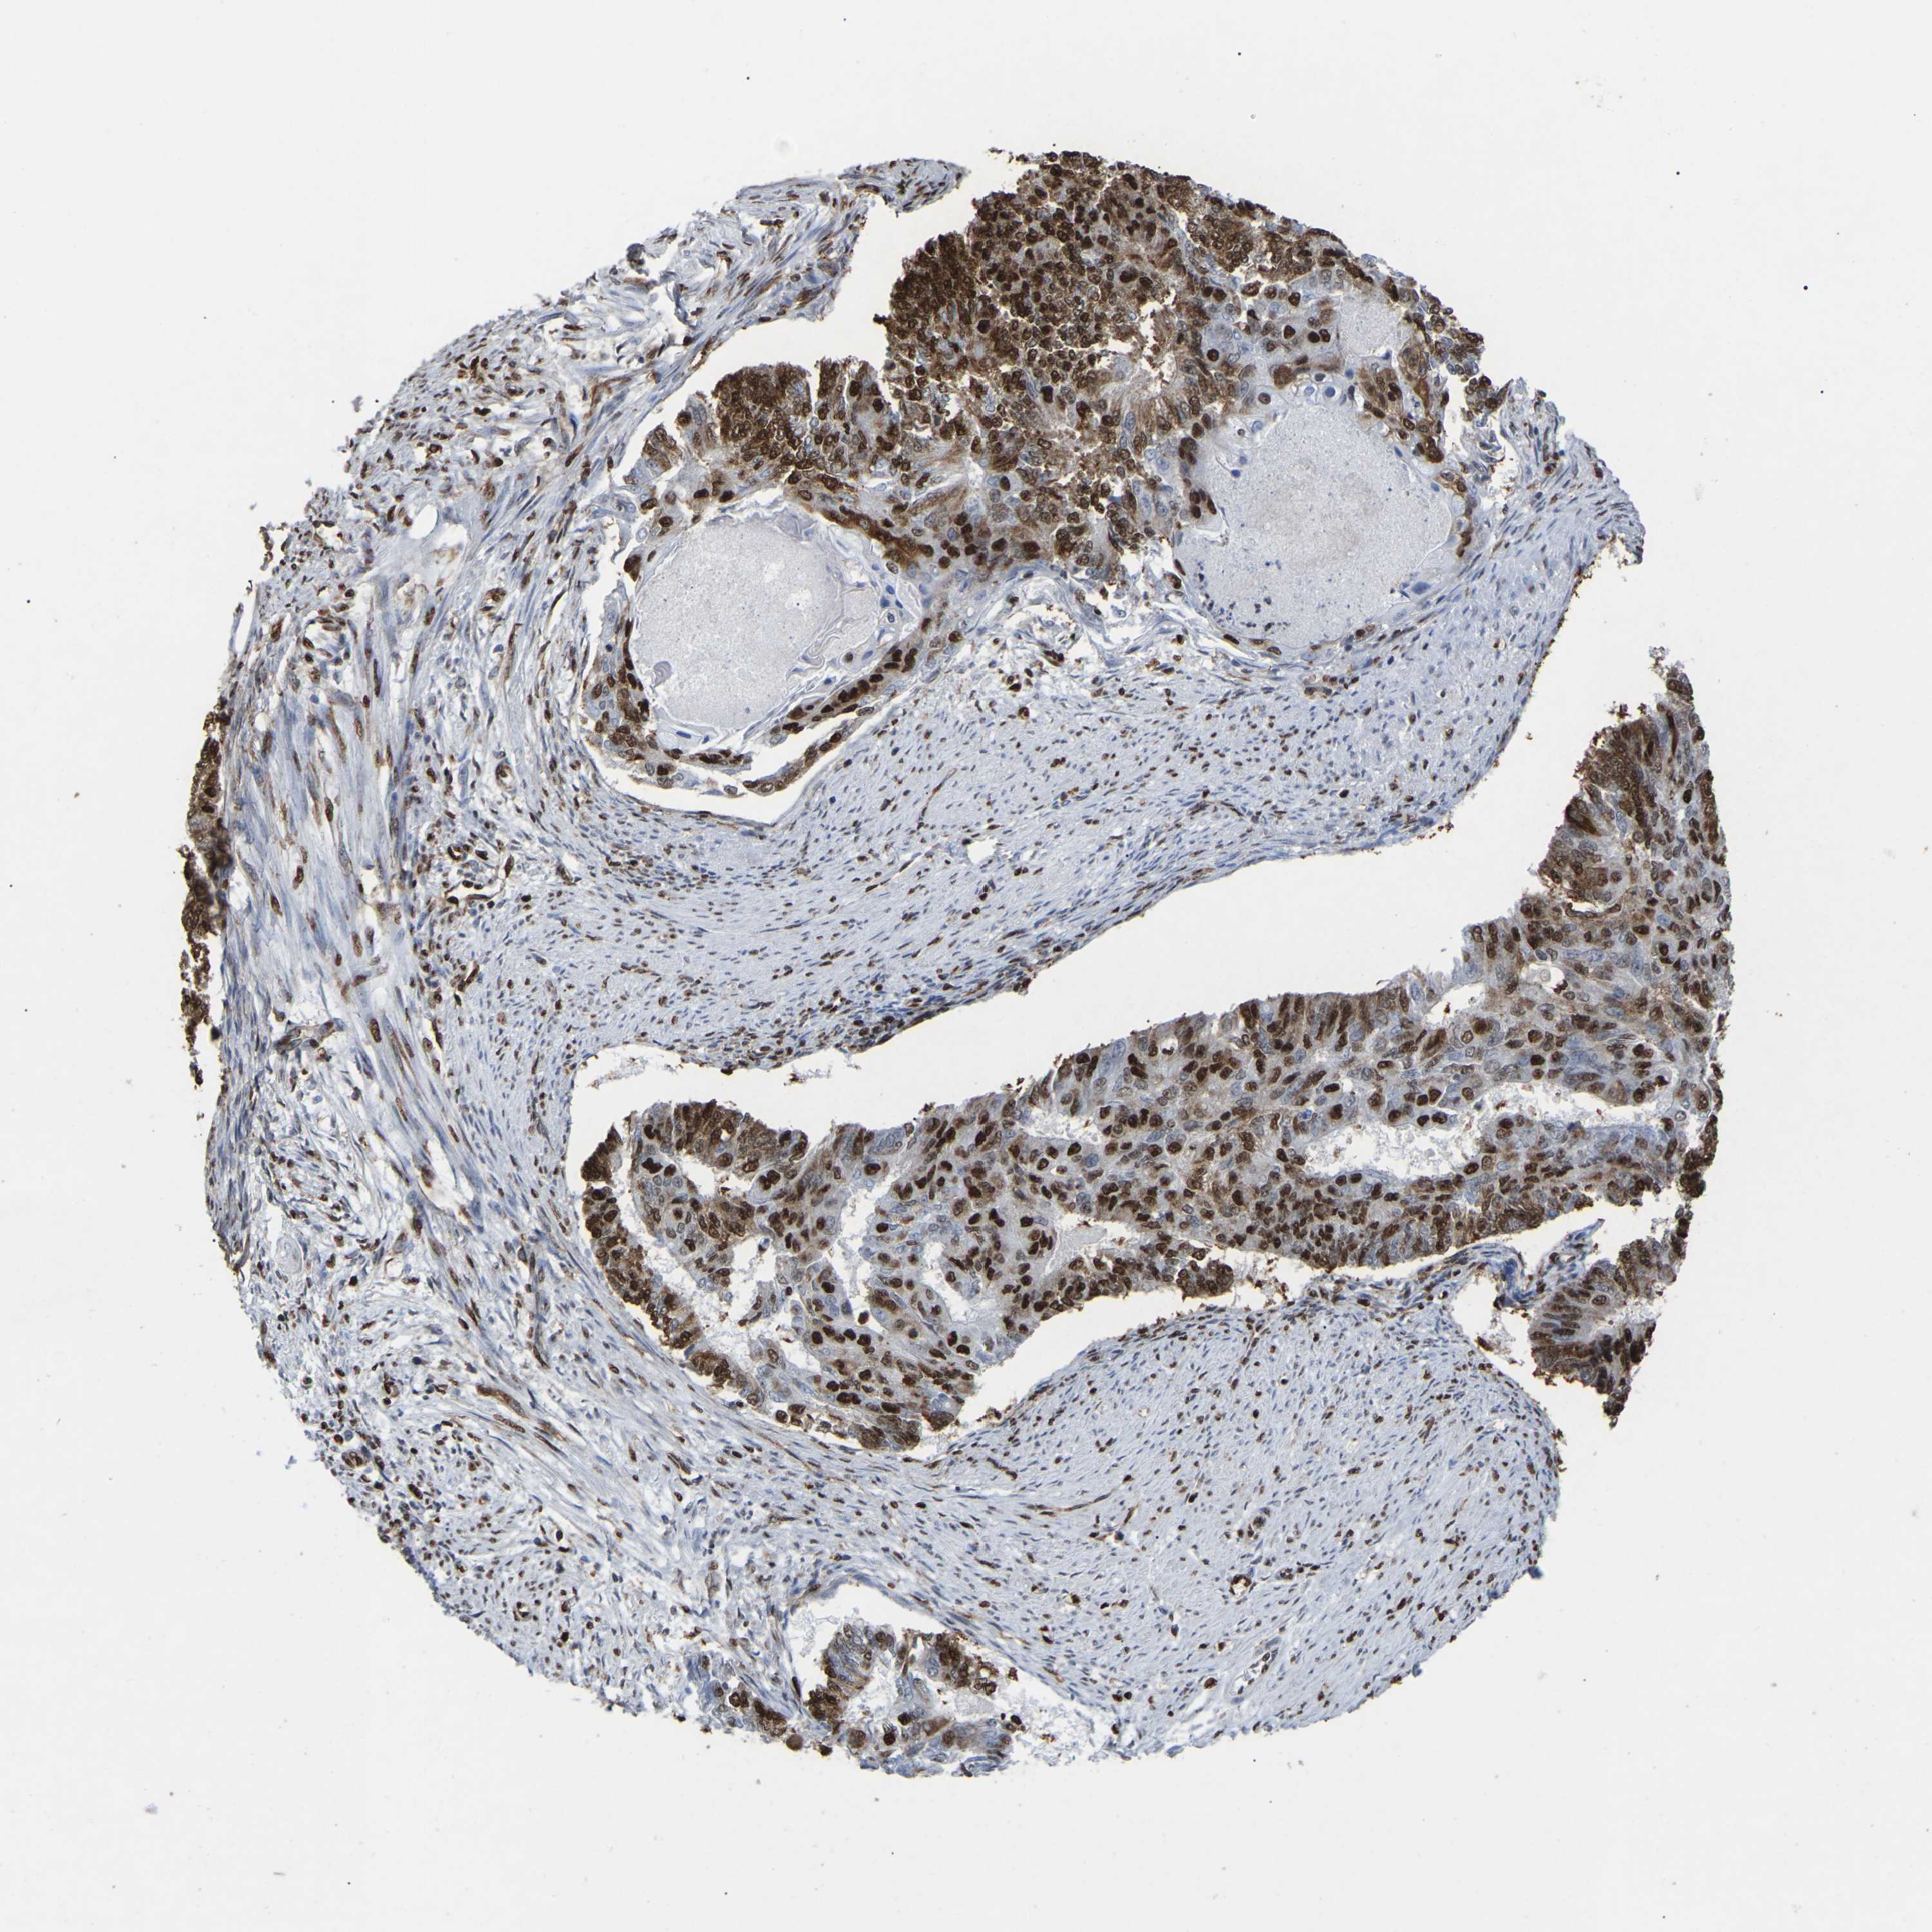

ENDOMETRIAL CANCER - Protein expressioni

A mouse-over function shows sample information and annotation data. Click on an image to view it in a full screen mode. Samples can be filtered based on level of antibody staining by selecting one or several of the following categories: high, medium, low and not detected. The assay and annotation is described here.

Note that samples used for immunohistochemistry by the Human Protein Atlas do not correspond to samples in the TCGA dataset.

Antibody stainingi

Antibody staining in the annotated cell types in the current human tissue is reported as not detected, low, medium, or high, based on conventional immunohistochemistry profiling in selected tissues. This score is based on the combination of the staining intensity and fraction of stained cells.

Each image is clickable and will lead to virtual microscopy that enables deeper exploration of all samples and also displays staining intensity scores, fraction scores and subcellular localization as well as patient and tissue information for each sample.

Antibody HPA019703

Antibody CAB016547

Staining

High

Medium

Low

Not detected

Intensity

Strong

Moderate

Weak

Negative

Quantity

>75%

75%-25%

<25%

None

Location

Nuclear

Cytoplasmic/membranous

Cytoplasmic/membranous,nuclear

Adenocarcinoma, NOS

Adenoma, NOS